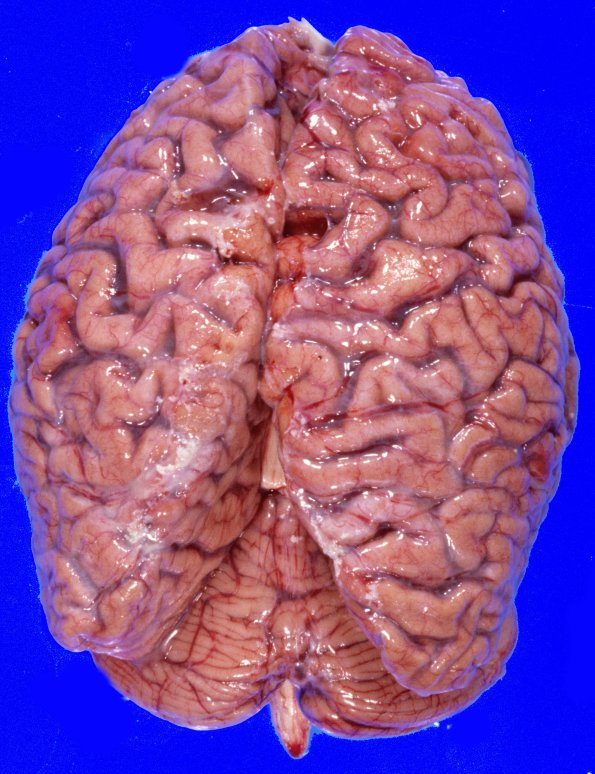

The unfixed frontal and parietal gyri appear somewhat atrophic, the temporal minimally so, and the occipital lobe is essentially normal.